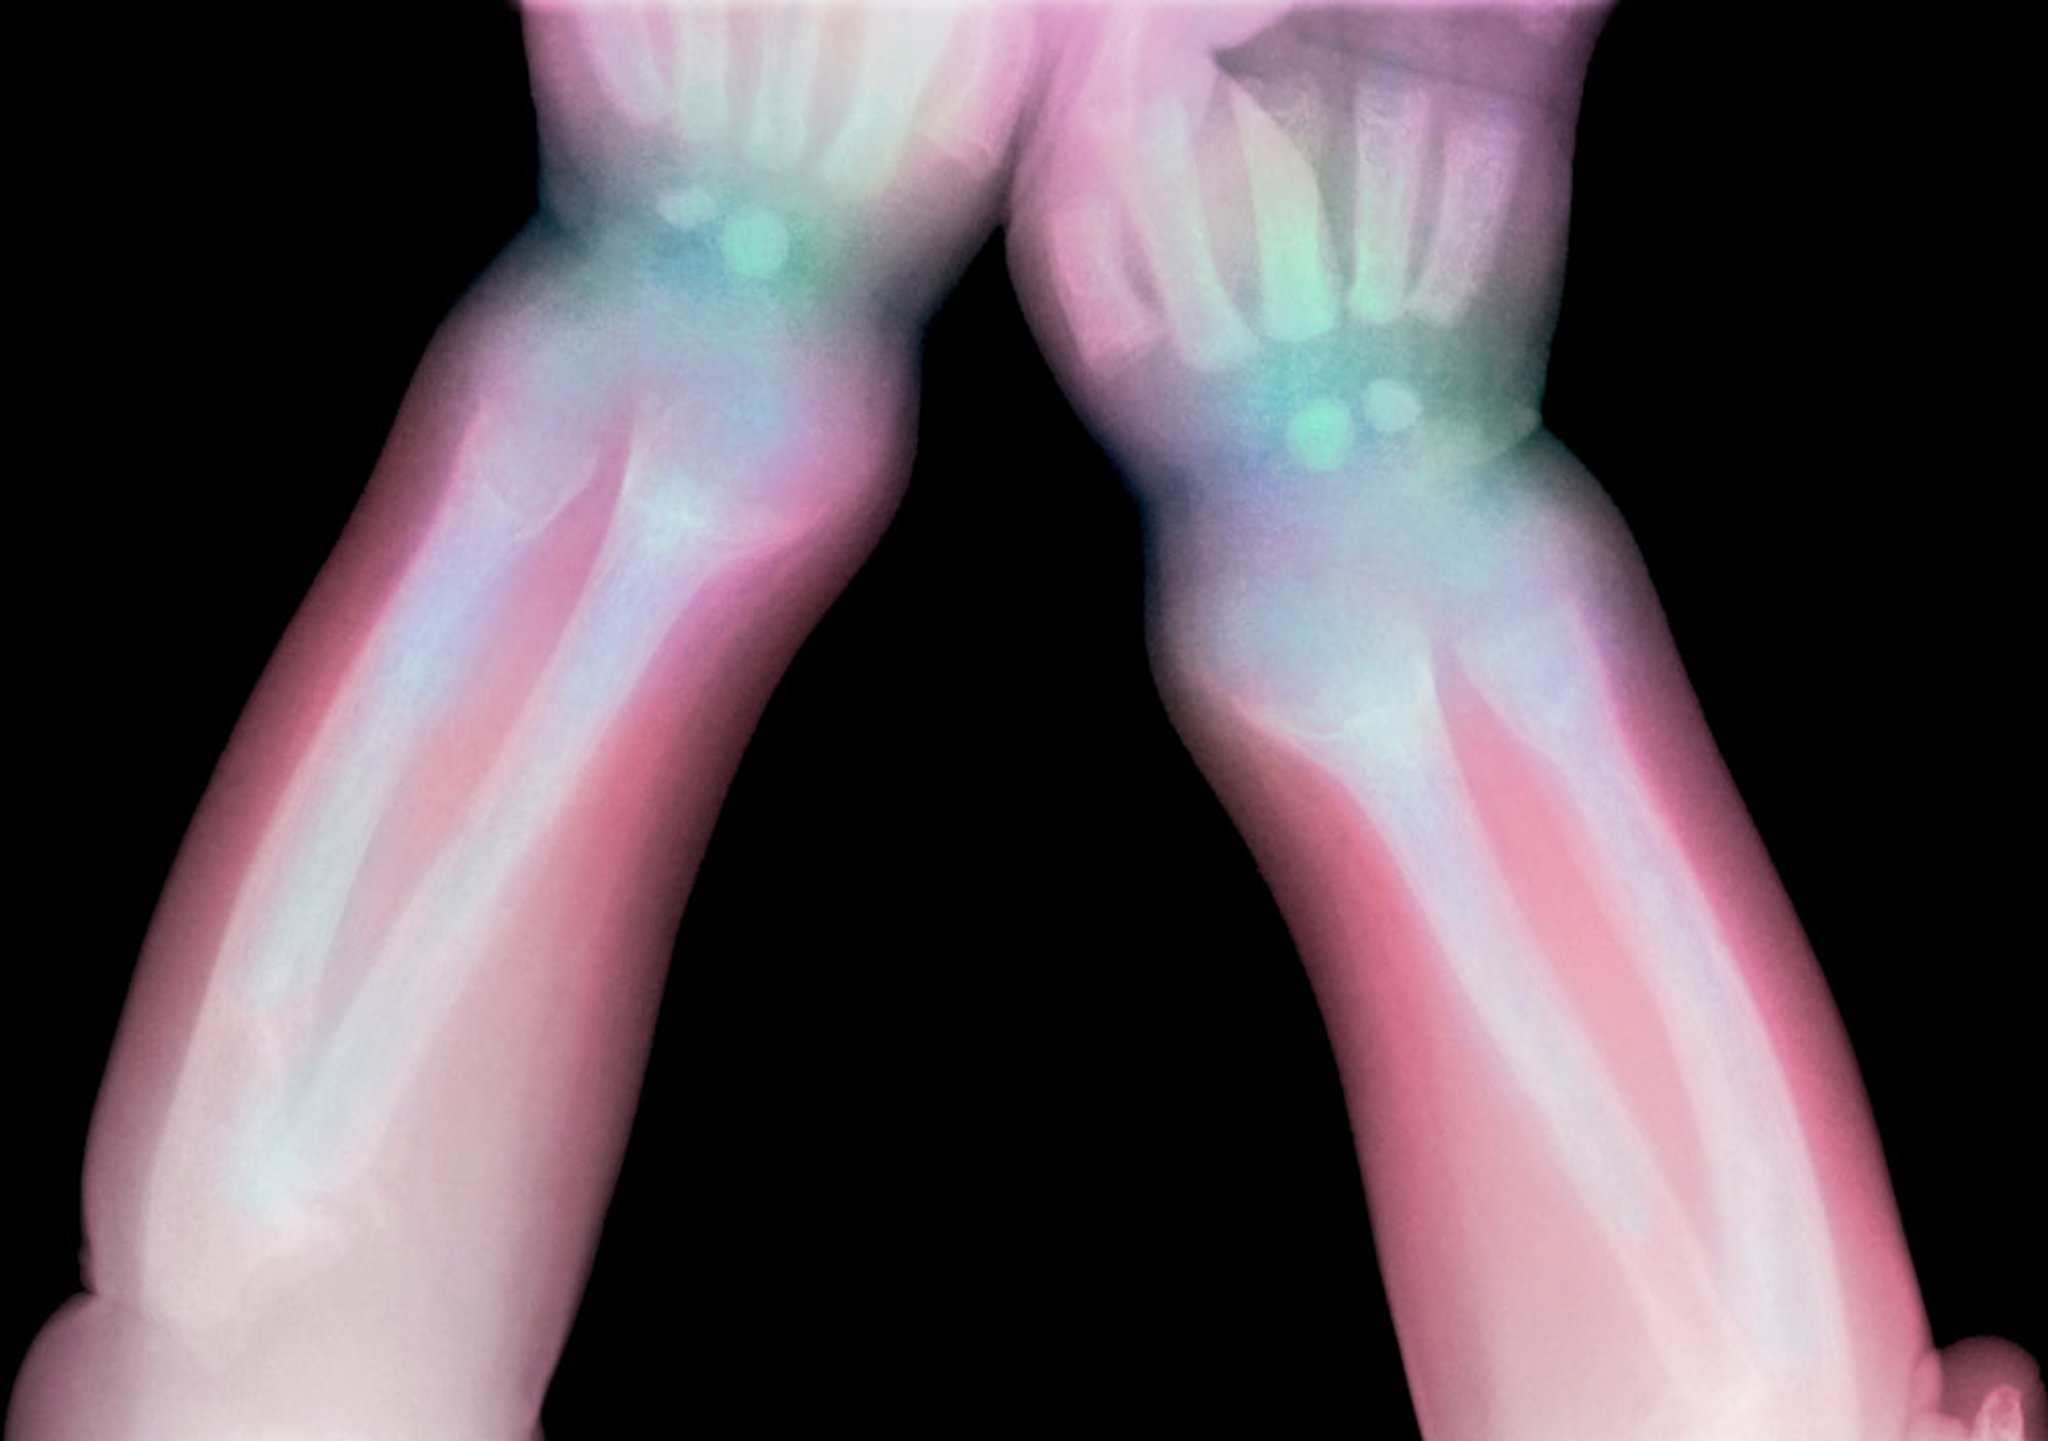

Questa radiografia mostra una lucenza del radio distale e dell'ulna in un bambino con rachitismo.